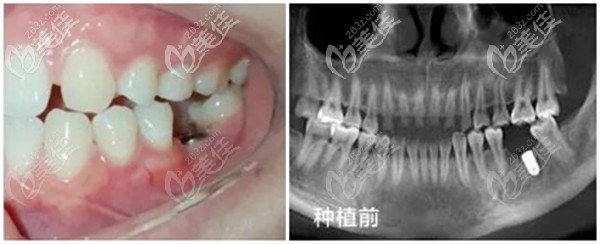

術(shù)前照片:

種植前牙齒情況:左邊下頜一顆大牙齲壞、缺失;因從小喜歡吃甜食,口腔衛(wèi)生做的又不到位,導(dǎo)致左下第1磨牙齲壞,(淺齲的時(shí)候不重視,一拖再拖一直到蛀牙發(fā)展到無法保留),只能拔掉。

CBCT全景片檢查,牙槽骨可用骨高度約16.00mm、可用骨寬度約11.80mm,條件良好、無炎癥,符合做牙齒種植的需求。